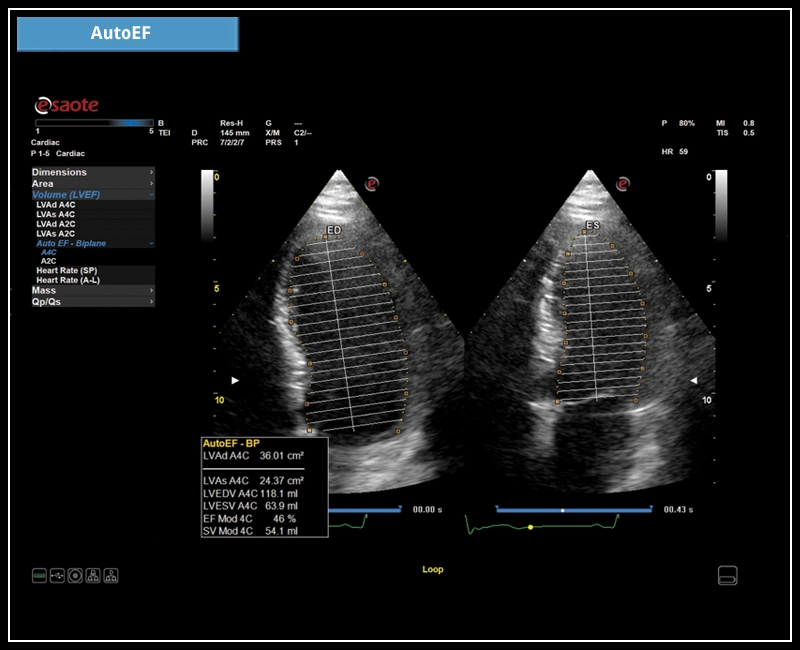

MyLab™E80 - AutoEF

MyLab™E80 - AutoEF

MyLab™Omega eXP - AutoEF

MyLab™Omega eXP - AutoEF

MyLab™X90 - AutoEF Automatic Ejection fraction assessment of the left ventricle

MyLab™X90 - AutoEF Automatic Ejection fraction assessment of the left ventricle

MyLab™X5 - AutoEF

MyLab™X5 - AutoEF

MyLab™X6 - AutoEF

MyLab™X6 - AutoEF

MyLab™X7 - AutoEF

MyLab™X7 - AutoEF

MyLab™A50 - AutoEF

MyLab™A50 - AutoEF

MyLab™A70 - AutoEF

MyLab™A70 - AutoEF